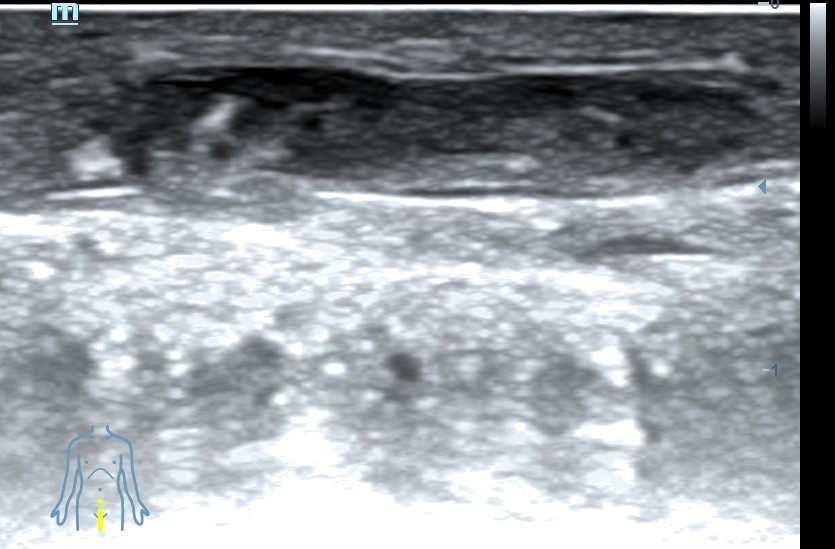

Ecografía clínica pene: se visualiza vena dorsal rellena de material hipoecogénico heterogéneo, no compresible, no flujo con Doppler color.

Diagnóstico: Trombosis vena dorsal del pene.